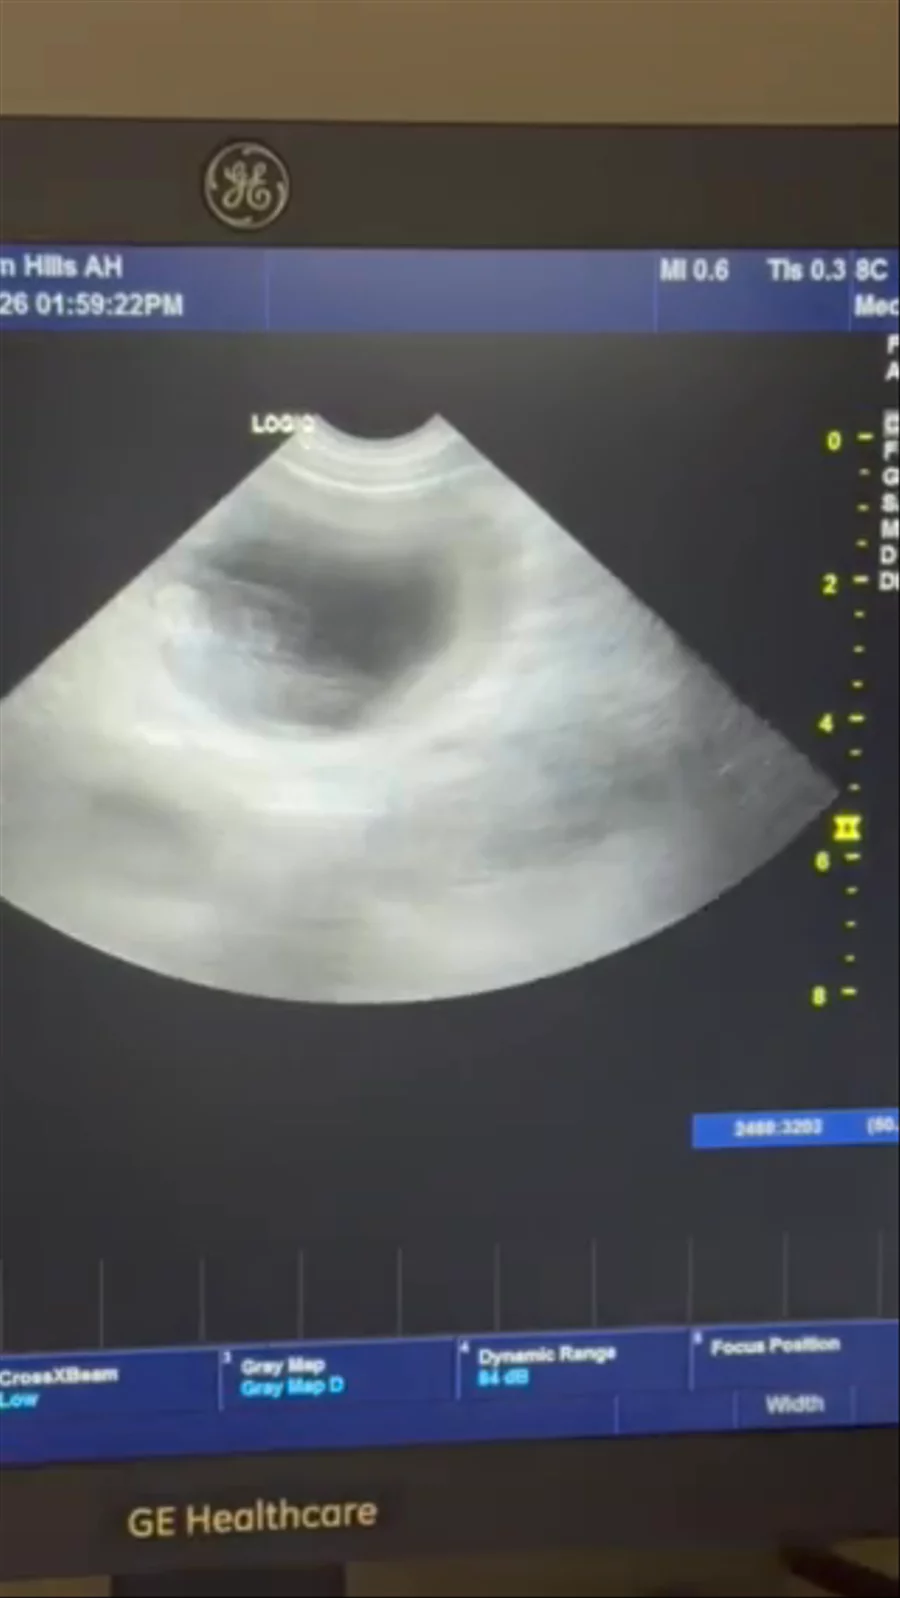

We have confirmed babies with Angel🤍🪽 X Diesel🖤✨🤩🤩🤩🤩🤩 omg I’m so excited!!! You can see the babies and their hearts beating🥹🥹🥹